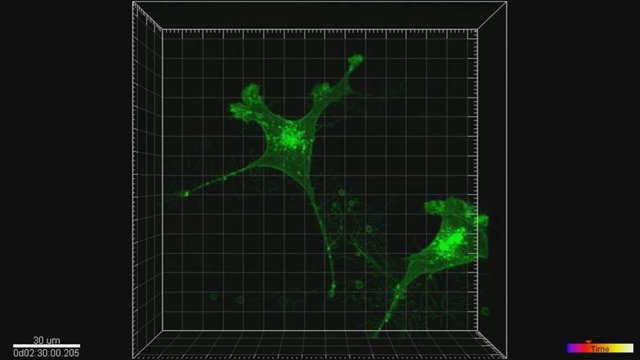

Scientists from Beijing Institute of Technology loaded cells in Tianzhou-1 for experiment. / CGTN Phot0

A group of Chinese scientists from the Beijing Institute of Technology have loaded human cells into a highly integrated and automated device on Tianzhou-1, with this question in mind: How will the cells be cultured and interact with its immune system in space?

Through comparison with experiment results on the ground, Chinese scientists can try to find out more on how the nervous and the immune system interact in space's microgravity environment.

Associate Professor Li Xiaoqiong says this bioscience space experiment will last about 2 weeks. / CGTN Photo

Li Xiaoqiong, associate professor from Beijing Institute of Technology, told CGTN that space will provide a special environment for the cells, one is microgravity, the other is radiation.

This time, they have put the cells on this micro-fluidic chip, and all the micro experiments will be carried out on it with the help of remote control. Li said the device is now in stable operation.